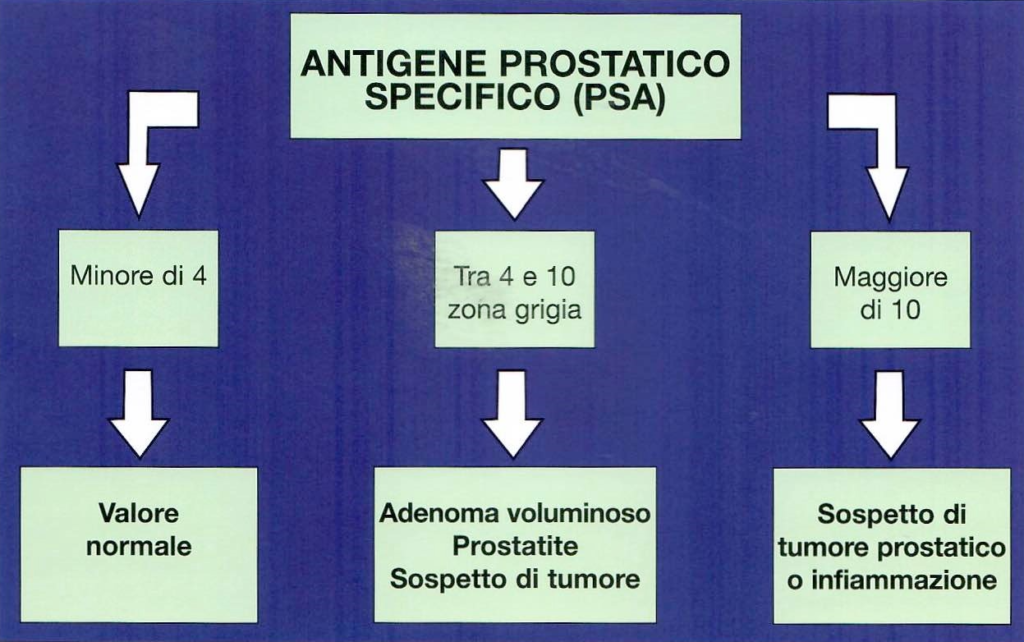

Ma cos'è questo PSA: qual è la sua funzione, qual è il significato del suo aumento nel sangue, che valori deve avere per essere considerato normale, e se ha valori alterati cosa ci può essere?

Abbiamo visto come la prostata sia costituita da un insieme di ghiandole situate sotto la vescica attorno al canale che porta fuori l'urina dall'uretra. Abbiamo prima parlato di manicotto ed anche visto come la funzione di queste ghiandole sia quella di fabbricare il liquido in cui vengono custoditi e veicolati gli spermatozoi; inoltre essi producono anche una sostanza specifica che serve a ritardare la coagulazione e l'essiccamento del liquido seminale fuori dall'organismo. Questa sostanza si chiama Antigene Prostatico Specifico (PSA). Solo quindi le ghiandole della prostata producono il PSA ed è per questo che il PSA È SPECIFICO DELLA PROSTATA.

La maggior parte del PSA è presente nel liquido seminale ma una piccola quantità si diffonde nel sangue dove è possibile rintracciarla e dosarla. La presenza del PSA nel sangue tende ad aumentare con l'età tanto che nell'anziano il quantitativo di PSA nel sangue è maggiore che nel giovane. Anche perché nell'anziano la prostata è di volume maggiore che nel giovane e quindi andiamo a sottolineare un altro concetto importante: più la prostata è grossa più possiamo avere un PSA aumentato dato che esso è prodotto dalle ghiandole prostatiche. Più ghiandole ci sono più ci può essere produzione di PSA.

Ma il PSA può essere più alto anche in altre situazioni che non hanno nulla a che vedere col tumore, come, per esempio, l'ingrandimento benigno della prostata, le infezioni o infiammazioni ed altre ragioni che ci sfuggono.

Fatto il prelievo di sangue mi reco a ritirare la risposta: se i valori di riferimento sono da 0 a 4 tutto bene.

Con valori superiori che debbo fare, quale sarà il mio destino?

Per valori superiori a 4 è consigliabile una visita specialistica dall'urologo che mi visiterà la prostata. Se nella mia famiglia ci sono stati casi di tumore prostatico, mi reco a fare una visita anche per valori superiori a 3.